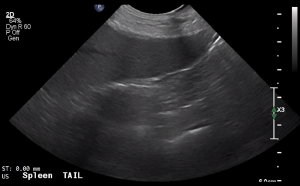

SIMON Ultrasound Database

This ultrasound database is a free resource for students and doctors!

Our collection includes videos of dogs, cats, horses, cows, humans, and many other species!